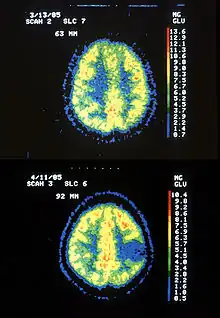

| Two PET images—the upper of which shows a normal brain and the lower shows astrocytoma | |